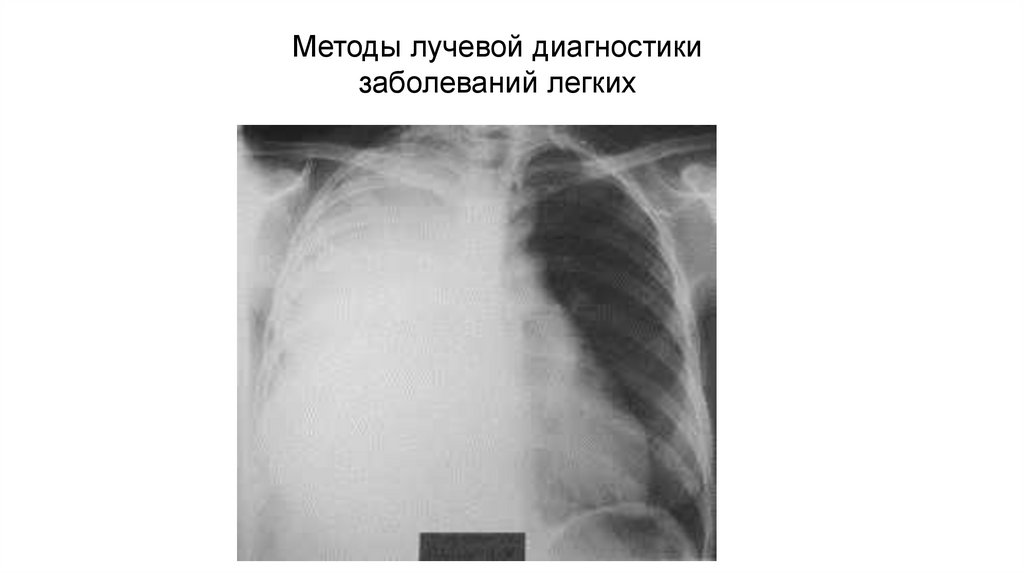

Трапецивидная конфигурация сердца